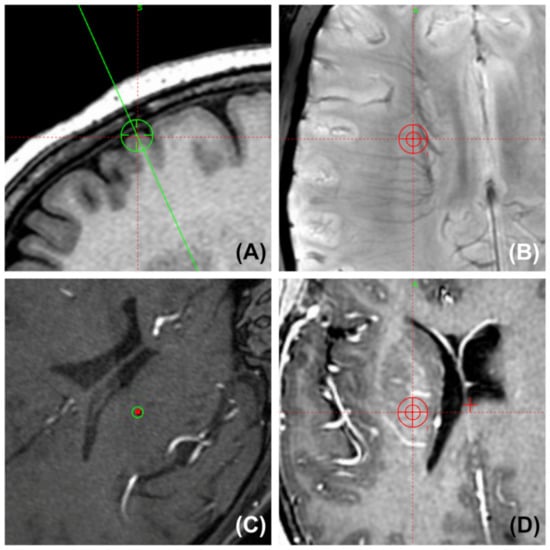

Most of the electrodes were unintentionally kept away from large intracranial arteries in both the hole-based trajectory and imaging-based trajectory cases for commonly used nuclei. A simulated trajectory for the STN and the cerebral arteries on 3D MRA are shown in Figure 6. Moreover, the small veins in the subcortex and the arteries in the sulci and fissures were easily bypassed at close range by the cannula. Some planned trajectories and their surrounding vessels in various MRI sequences are shown in Figure 7.

Figure 7.

Surgical planning snapshot images show the position of the planned trajectory and its surrounding vessels (two-dimensional probe’s-eye trajectory visualization by SWI, TOF MRA, and T1W-Gd). (A) The entry point is always placed anterior to the coronal suture to avoid injuring the motor region. (B) Preventing the guide tube from puncturing small and deep vessels in the corona radiata by SWI. (C) Confirming that the trajectory was kept far from the arteries in the lateral fissure by TOF MRA. (D) Gadolinium-enhanced MRI shows that the trajectory was kept at a distance from the surrounding arteries and veins in the basal ganglia area.